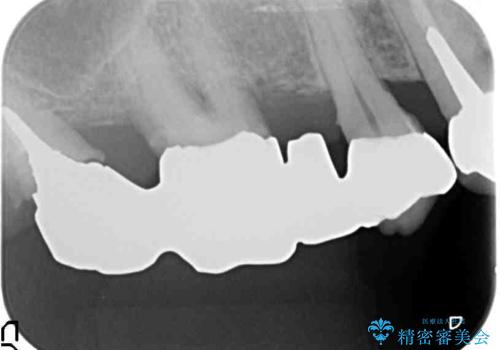

検査の結果、感染根管や欠損、歯周病により残すことのできない歯、等多々問題が認められます。

残すことのできる歯できない歯を選別し、欠損部にはインプラントによる咬合機能の回復、保存できる歯には歯周病治療・根管治療を行う治療計画としました。